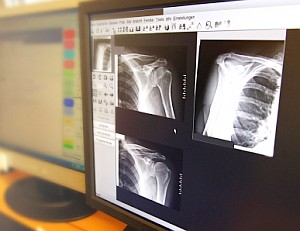

Digitale Röntgenbilder: Radiologenroutine im Umbruch (Foto: pixelio.de/Sturm) |

Wien (pte004/30.11.2011/06:10) Ultraschall- oder Röntgenuntersuchungen werden im Zeitalter von E-Health zunehmend digital. Bisher deuten alle Prognosen darauf, dass E-Health als Sammelbegriff für den Computer- und Interneteinsatz in der Medizin die ärztliche Routinen neu strukturieren wird (pressetext berichtete: http://pressetext.com/news/20111006015 ). Welche Änderungen der Trend zur Digitalisierung für die Radiologie bringt, erklärt Alexander Gürtler, Datenexperte bei A1 Telekom http://a1.net , im pressetext-Interview anlässlich einer Conect-Expertenveranstaltung http://conect.at in Wien.